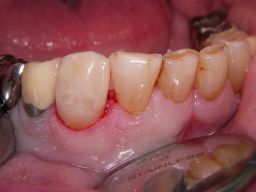

![]() | Der Eckzahn (Zahn 43) in der Mitte des Bildes zeigt an mehreren Stellen am Füllungsrand schwarze Karies, wie man hier aus verschiedenen Perspektiven sieht. Der Zahn rechts daneben auf dem Foto (Zahn 42) zeigt eine schwarze Randverfärbung einer älteren Kunststofffüllung. |

![]() | |||||||||||||||||||||||||||||||||||||||||||||||||||||||||||||||||||||||

Links das Ergebnis am rechten Eckzahn im Unterkiefer nach Ersatz beider Füllungen. Am benachbarten Zahn 42 wurde die Rand- und Füllungsverfärbung einfach durch Politur entfernt - eine Erneuerung der Füllung war nicht notwendig. Eine Zuzahlung für den Kassenpatienten ist hier nicht angefallen. Alle Defekte des Eckzahnes zusammengenommen sind so groß, daß man sicherlich auch eine Krone hätte vertreten können. | |||||||||||||||||||||||||||||||||||||||||||||||||||||||||||||||||||||||||